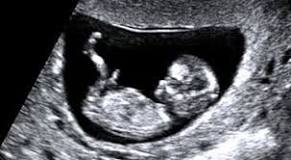

| About 58,600,000 results All pregnant women are offered an ultrasound scan at around 8-14 weeks of pregnancy. This scan is called the dating scan. It's used to see how far along in your pregnancy you are and check your baby's development. Your midwife or doctor will book you a dating scan appointment. Dating ultrasound baby scan - Pregnancy and baby guide - NHS ...www.nhs.uk/.../dating-scan-ultrasound-10-11-12-13-weeks-pregnant.aspx Dating scan - BabyCentrehttps://www.babycentre.co.uk/a557403/dating-scan The scan will usually show that your pregnancy is less far along than suggested by your LMP. This means that accurate dating reduces your chance of having ... Dating scan | Pregnancy Birth and Babywww.pregnancybirthbaby.org.au/dating-scan Dating scan. Print. A dating scan is an ultrasound scan to determine how many weeks pregnant you are and your due date. Read on for more information about what a dating scan offers. Dating scans are used to confirm how many weeks pregnant you are and your expected due date.Dating and viability - Ultrasound Carewww.ultrasoundcare.com.au/.../pregnancy-ultrasound-5-17-weeks-dating- and-viability.html A dating scan is an ultrasound examination which is performed in order to establish the gestational age of the pregnancy. Dating scans also reveal other important information such as: the number of fetuses and gestation sacs. the presence of a heart beat. the size of the fetus, from which the gestational age is ...Dating ultrasound baby scan - Pregnancy and baby guide - NHS ...www.nhs.uk/.../dating-scan-ultrasound-10-11-12-13-weeks-pregnant.aspx All pregnant women are offered an ultrasound scan at around 8-14 weeks of pregnancy. This scan is called the dating scan. It's used to see how far along in your ... Too early for a dating scan? - March 2013 - BabyCenter Australiahttps://www.babycenter.com.au/thread/.../too-early-for-a-dating-scan Hi all, Im 6 weeks today and just went to have my dating scan. ... at 7 weeks wait until 8 weeks :-) baby should def have heartbeat by then :-). Dating scans - BabyCenter Australiahttps://www.babycenter.com.au/a557403/dating-scans When will I have my first scan? Is a dating scan accurate? What else will the dating scan reveal? What happens during the dating scan? How big will my baby be ... Early dating scans | Topics, Antenatal Screening, Pregnancy ...www.healthtalk.org/peoples-experiences/.../early-dating-scans All Trusts must ensure that they provide a dating scan, and an 18- 20 week fetal ... I mean I could work out the scan of a gall-bladder or something, but I can ... 7 Week Pregnant Ultrasound Scan - Huggieshttps://www.huggies.com.au/pregnancy/week-by-week/.../7-week This is a scan or ultrasound which determines your expected date of confinement ... though obviously important, are not the primary means of measuring growth. 12 week scan - Dating scan | Mumsnethttps://www.mumsnet.com/pregnancy/12-week-scan The dating scan is usually done at some point between 8 weeks and 14 weeks. ... have a full bladder, as this puts the uterus in a better position to be scanned. dating scan say im only 9 weeks!!! can anyone help? - Netmumshttps://www.netmums.com/.../99349-dating-scan-say-im-only-9-weeks-can- anyone-help-all.html I had my dating scan today, and I told them my 1st day of LMP ... i know what you mean though with this one my dates now don't add up ... | ||